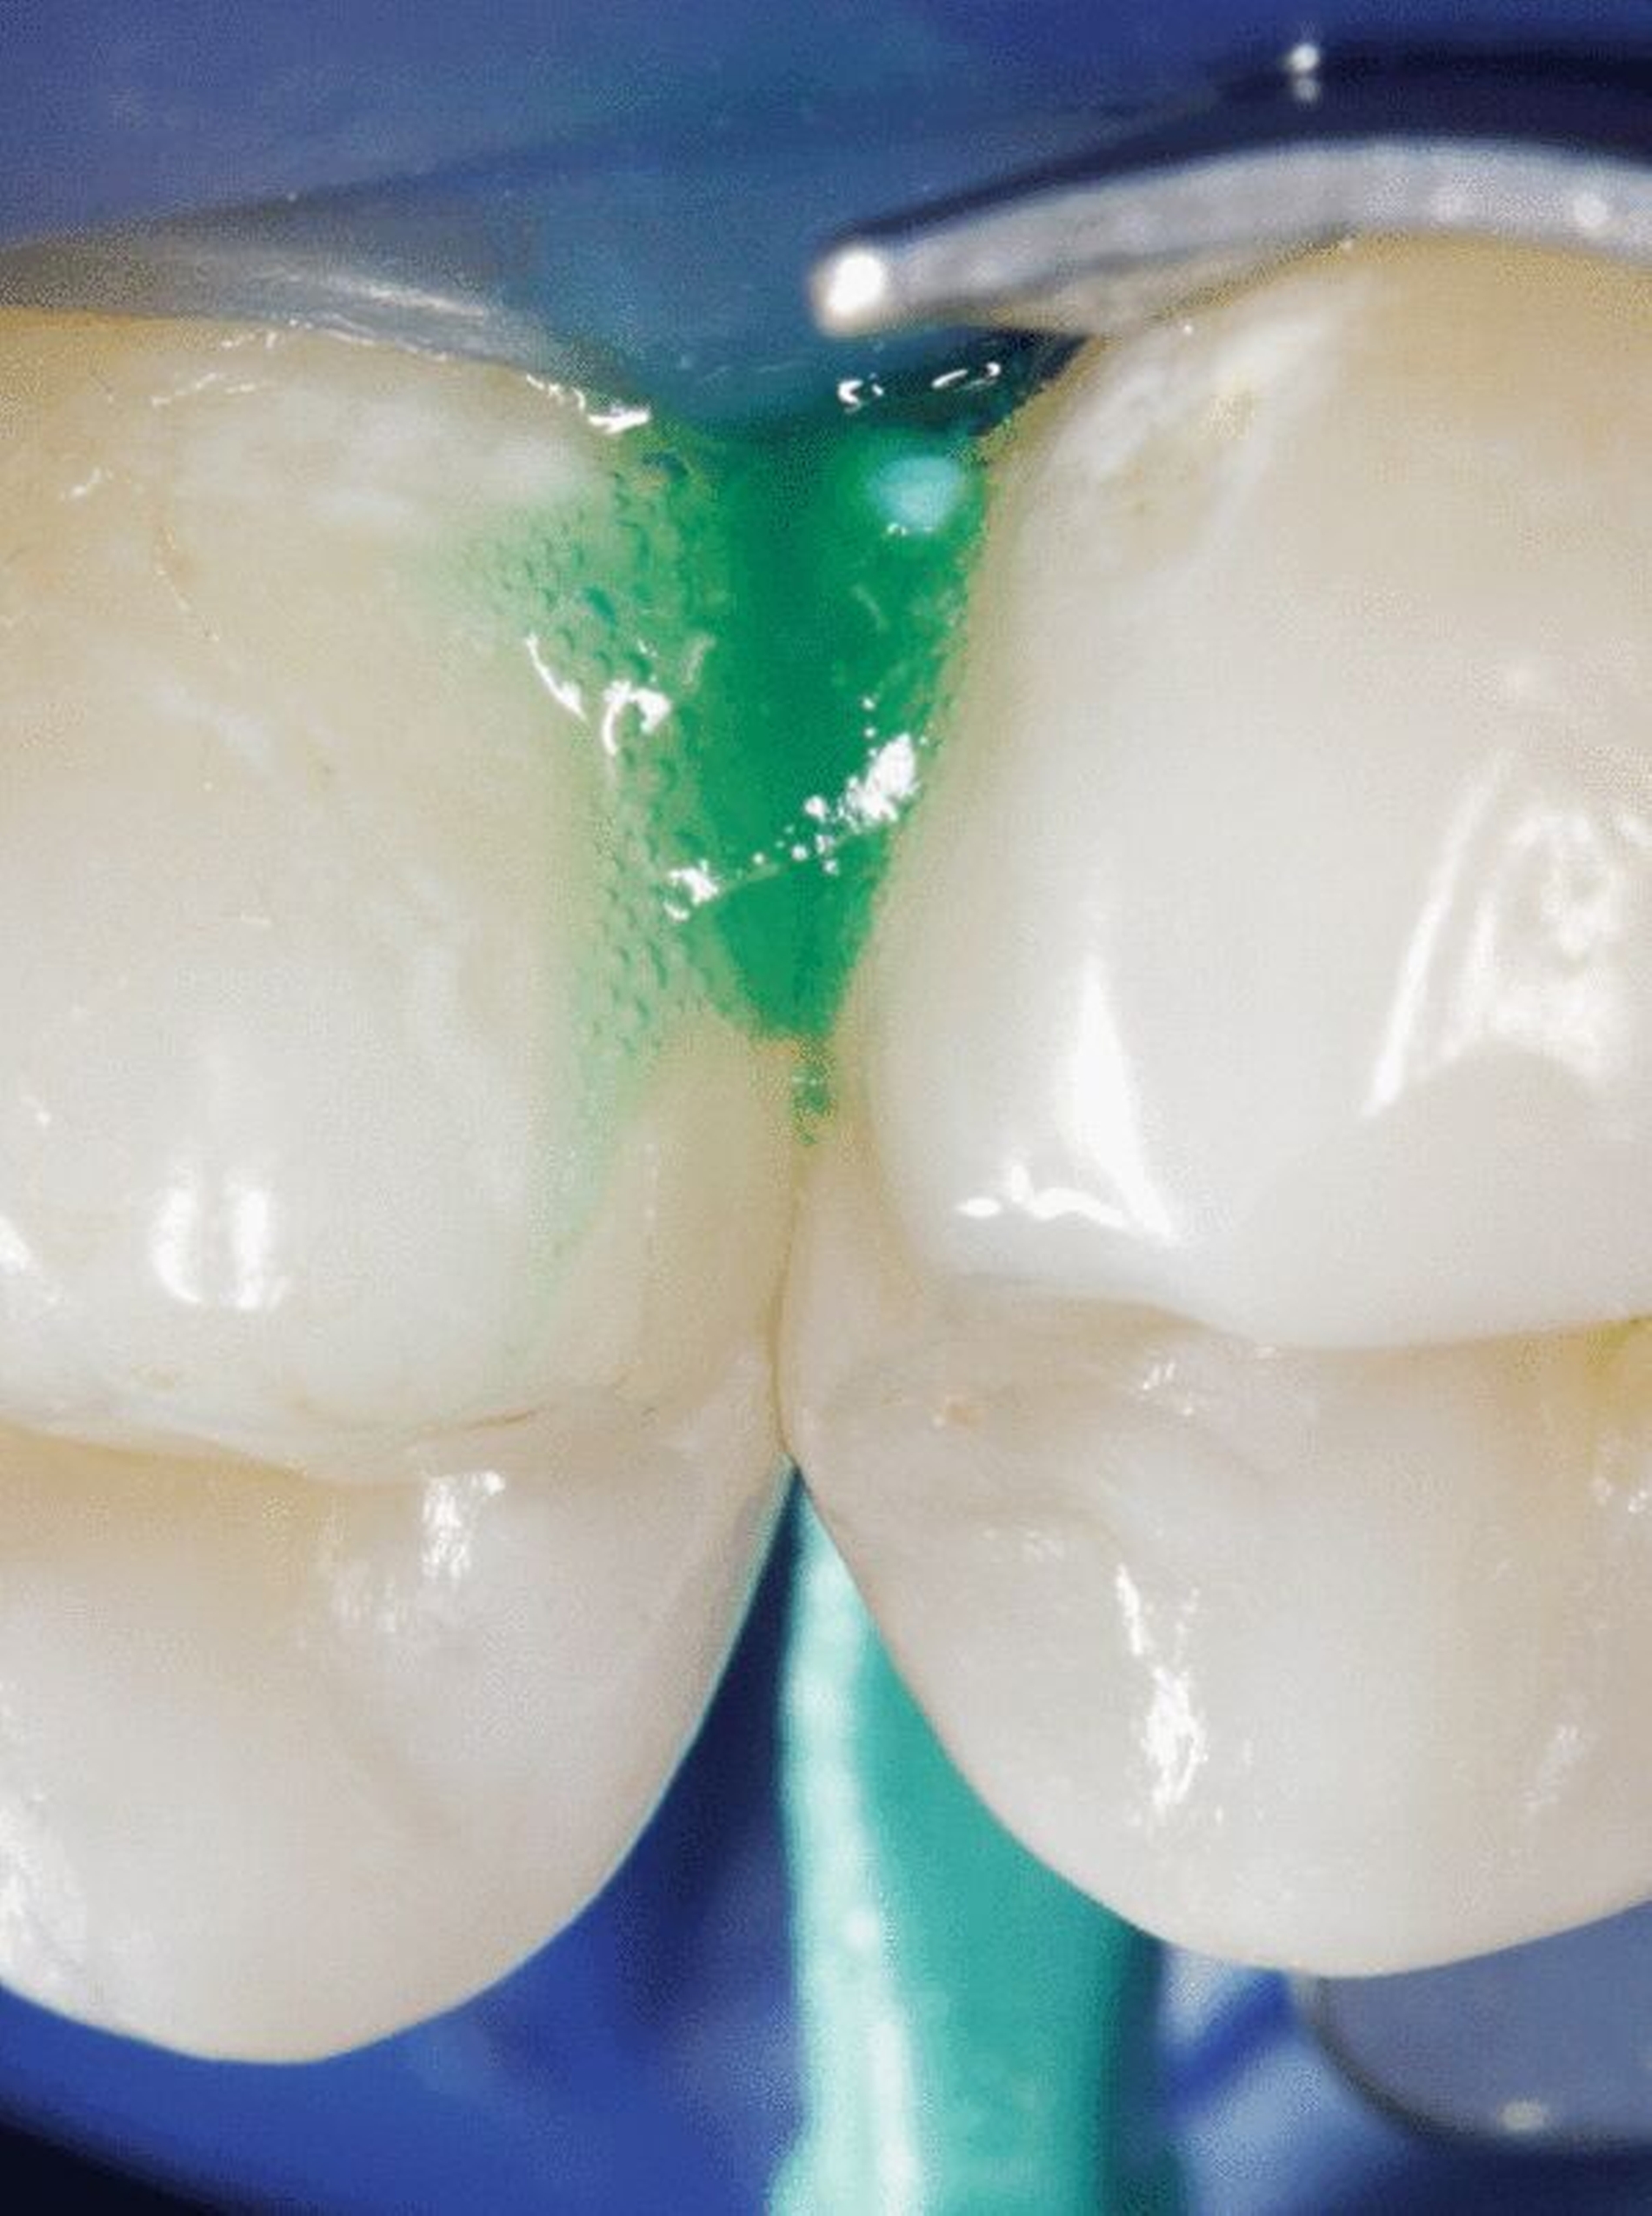

Bei der Kariesinfiltration wird die kariöse Zahnoberfläche mittels 15-prozentiger Salzsäure konditioniert und die Läsion getrocknet. Hiernach werden fließfähige Kunststoffe (Infiltranten) aufgetragen, die in die poröse Struktur des Läsionskörpers einer Karies eindringen. Nach der Aushärtung versiegelt der Infiltrant die Karies gewissermaßen intern, wodurch eine weitere Kariesprogression verhindert wird [Meyer-Lückel, 2012a]. Dies ist prinzipiell auch an allen anderen Zahnflächen durchführbar, allerdings sollte man sich immer die Frage stellen, ob es sich um eine aktive (progrediente) und damit behandlungsbedürftige Karies handelt. Darüber hinaus kann durch Infiltration bei ästhetisch störenden „White-Spot-Läsionen“ ein Maskierungseffekt erzielt werden.

Bisher gibt es ein Produkt zur Kariesinfiltration (Icon, DMG, Hamburg), das alle relevanten Agenzien (HCl-Gel 15 Prozent, Ethanol 99 Prozent und Infiltrant) und ein Keilchen zur Separation enthält. Allerdings sollte vor der Behandlung nach dem Legen von Kofferdam und der Verwendung des Keilchens unbedingt mittels Sondierung [Paris et al., 2019] nochmals darauf geachtet werden, dass nicht versehentlich eine kavitierte Läsion behandelt wird, da selbst Mikrokavitationen nur unzureichend mit dem Infiltranten aufgefüllt werden können und somit die Läsion nur unzureichend arretiert bleibt.

Insofern an benachbarten approximalen Flächen nur eine zu infiltrierende Karies vorliegt, empfiehlt sich die Benutzung des in der Packung befindlichen Folienbügelhalters (Icon, DMG, Hamburg), der mithilfe abgeflachter Keilchen approximal eingebracht wird (Abbildung 1a). Es ist also keine vorherige aufwendige Separation der Zähne notwendig; die Behandlung erfolgt in einer Sitzung. Wenn an benachbarten Approximalflächen zu infiltrierende Läsionen diagnostiziert werden, können diese ohne Zuhilfenahme der Folienbügelhalter behandelt werden (Abbildungen 1b und 1c). Dies spart nicht nur Zeit, sondern auch Material, da neben der gleichzeitigen Behandlung von zwei Läsionen auch der Totraum der hierbei verwendeten Kanülen wesentlich kleiner ist als derjenige der Folienbügelhalter. Somit reduziert sich der Materialpreis pro behandelter Läsion deutlich. Eine Auflösung des approximalen Kontaktpunktes oder eine „Verklebung“ der approximalen Flächen ist bei gewissenhafter Entfernung des überschüssigen Kunststoffs vor der Lichthärtung nicht zu befürchten. Zur ausführlichen Beschreibung der Grundlagen, der Entwicklung und der Anwendung der Technik in Einzelschritten verweisen wir auf unsere Übersichtsarbeiten [Meyer-Lückel und Paris, 2011; Meyer-Lückel und Paris, 2012].